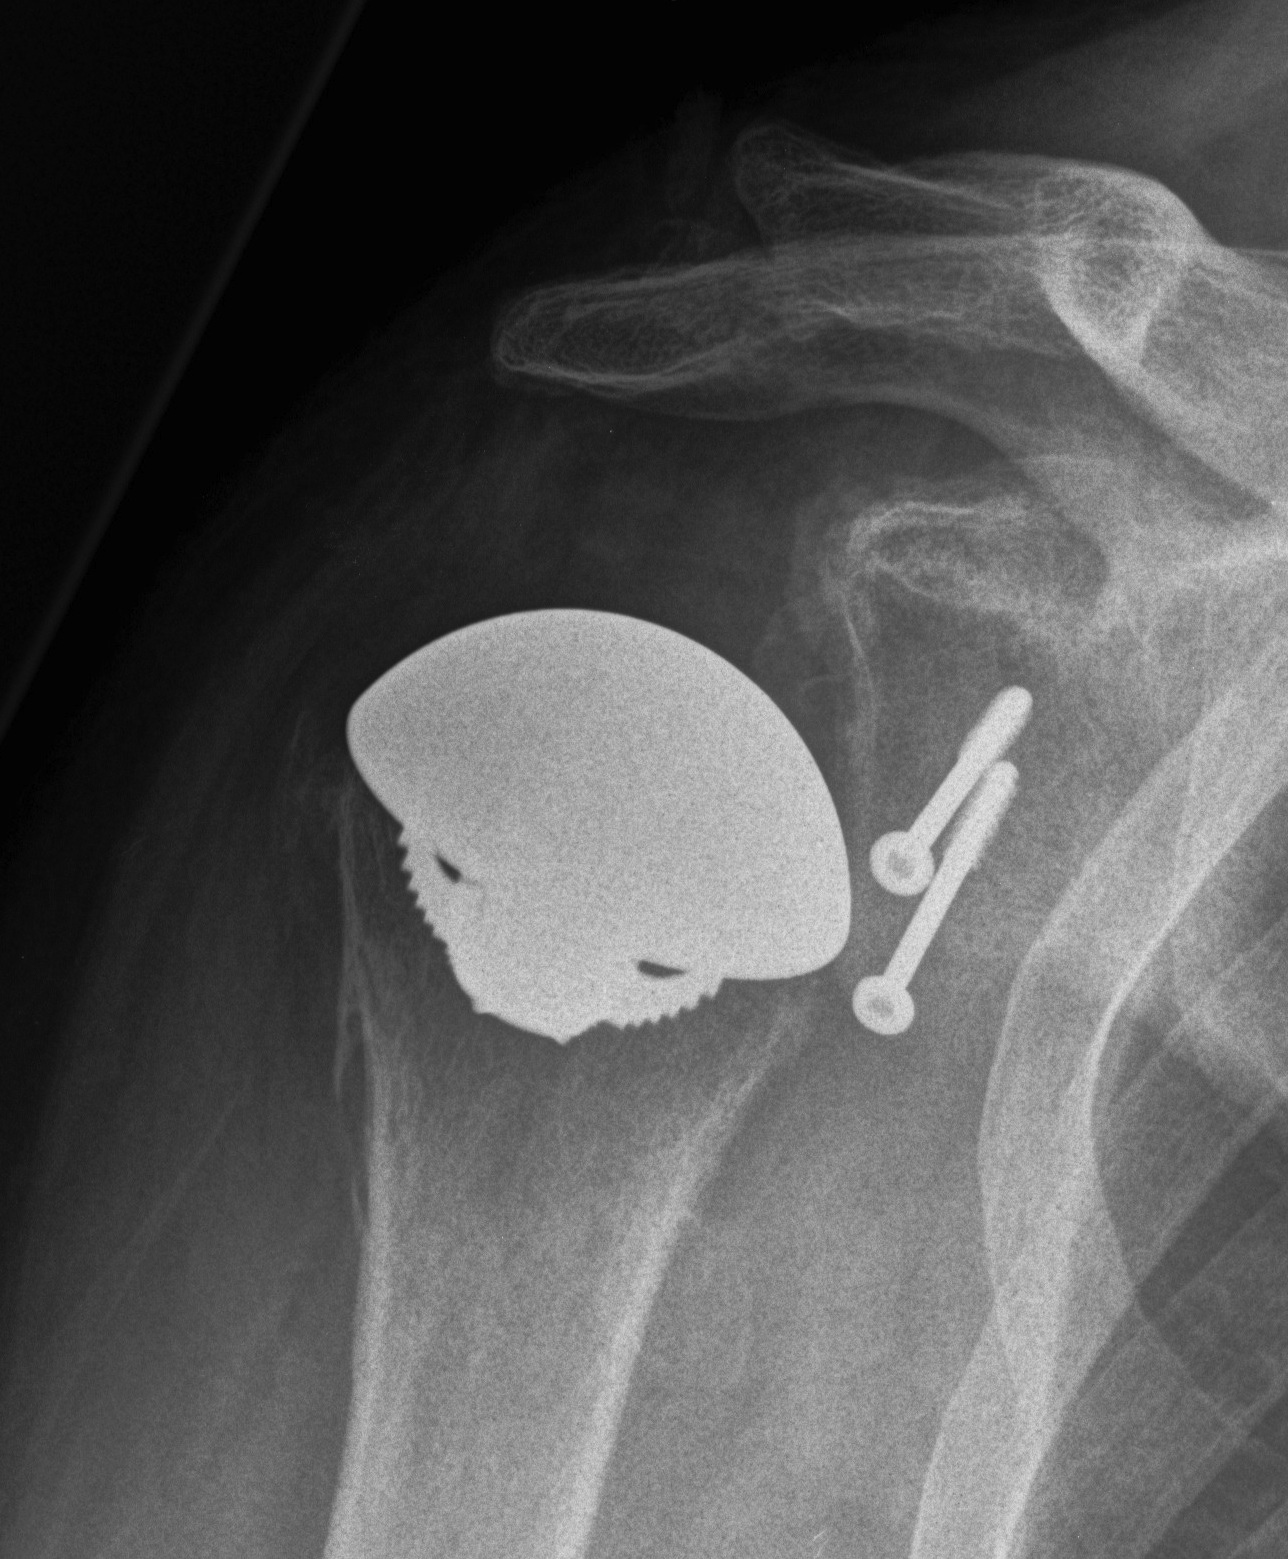

Humeral head replacement + glenoid autograft + rotator cuff repair

Post humeral head replacement / glenoid autograft / rotator cuff repair

Rotator cuff failure and development of anterosuperior escape